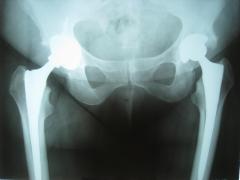

Αμφοτερόπλυερη ολική αρθροπλαστική ισχίου

Σε προχωρημένα στάδια ή λύση είναι χειρουργική. Σε ορισμένες περιτπώσεις και σε σχετικά νέους ασθενείς με οστεοαρθρίτιδα γόνατος μπορεί να γίνει οστεοτομία της κνήμης. Στις υπόλοιπες περιπτώσεις οστεοαρθρίτιδας γόνατος αλλά και ισχίου προτιμότερη θεραπεία είναι η ολική αρθροπλαστική. Υπάρχουν διάφοροι τύποι ολικών αρθροπλαστικών. Το χαρακτηριστικό τους είναι ότι ανακουφίζουν τον/την ασθενή από τον πόνο και έως κάποιο βαθμό βελτιώνουν και την κινητικότητά του.

Οι αρθροπλαστικές γίνονται με διάφορες μεθόδους αναισθησίας και η παραμονή στο νοσοκομείο είναι ολιγοήμερη. Η βάδιση με τη χρήση κάποιου υποβοηθητικού μέσου επιτρέπεται από τις πρώτες μέρες.